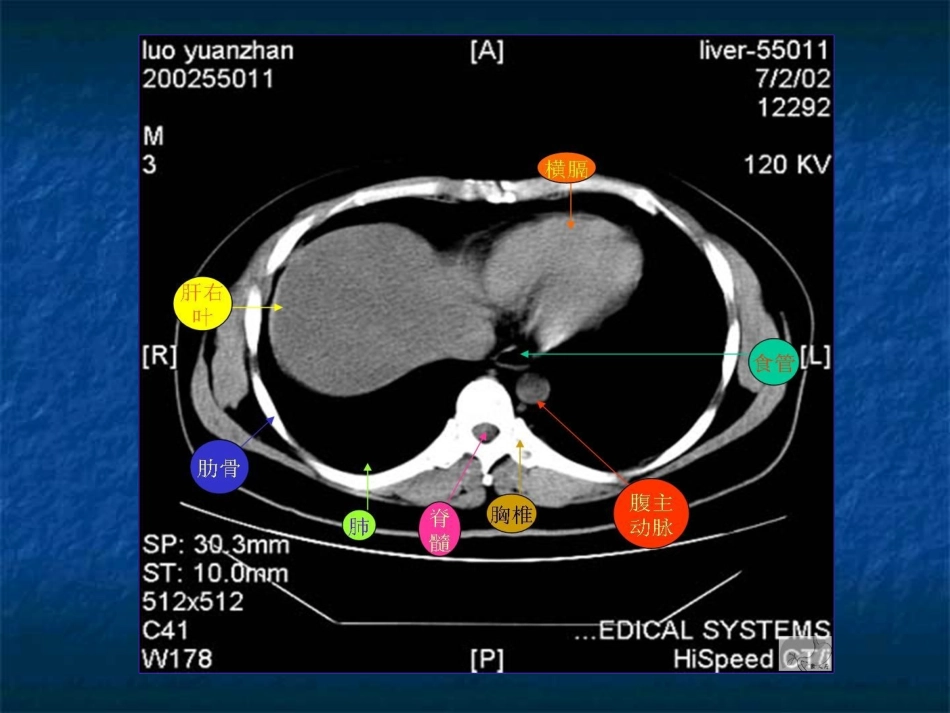

腹部腹部CTCT读片入门读片入门上上

腹部CT读片入门上